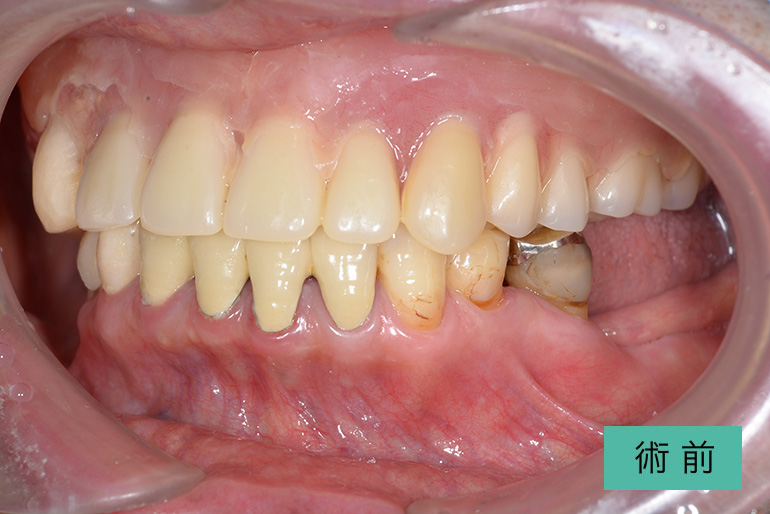

| 治療内容 | 上顎前歯右上3番から左上3番のセラミック冠 |

| 治療期間・回数 | 約1ヶ月、3回 |

| 費用(税込) | ¥990,000(165,000/1本)(補綴費用) ※自由診療 |

| リスク・副作用 | 疼痛、補綴物の脱落、咬合違和感、破折 |